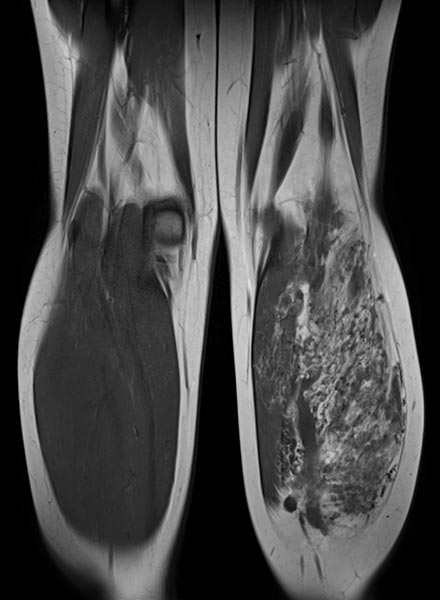

Coronal T1-weighted non-enhanced MRI shows an intramuscular, vascular lesion (isointense to the muscle) with marked interstitial hyperintense adipose tissue. This fatty tissue is more pronounced than would be usual in a normal venous malformation.

Axial T2-weighted MRI of the left lower leg shows multiple dilated, dysplastic veins in a venous malformation throughout the superficial flexor muscles. Slow flow causes stasis of the blood within the malformation with the formation of fluid-fluid levels. Almost the entire muscle consists of malformation and fatty tissue. Also visible is a large thrombus in a dilated, dysplastic vein.

In coronal, non-enhanced T1-weighted control MRI, the vascular component of the lesion is less conspicuous. However, clearly additional soft tissue remains that is pathologic (“salt-and-pepper pattern”). This tissue consists in part of hyperintense adipose tissue and in part of hypointense connective tissue. This is the typical MRI appearance of a fibro-adipose vascular anomaly (FAVA).

The vascular channels are largely occluded on axial control MRI in T2-weighted images. However, after successful occlusion of the vascular channels, a black-and-white “salt-and-pepper” pattern typical of FAVA remains. This consists of adipose tissue (hyperintense) and connective tissue (hypointense).